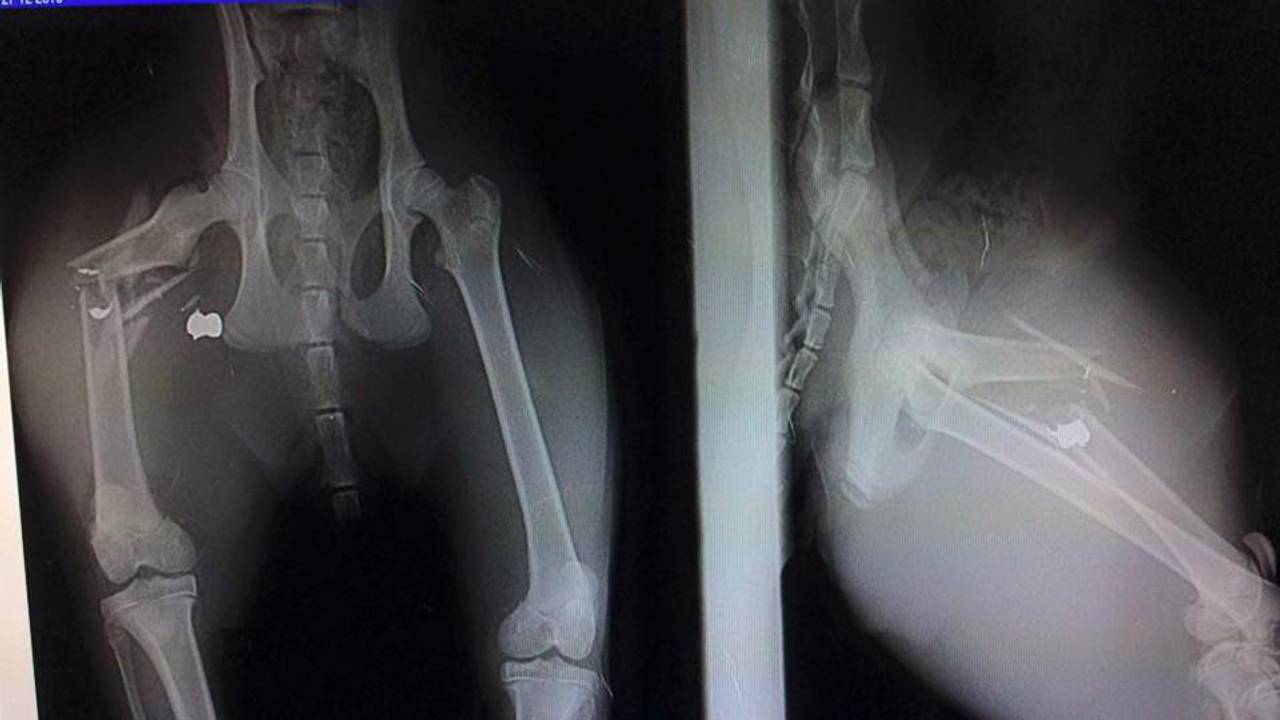

Kirsti Pol is verbijsterd. Zondagmorgen werd haar acht maanden oude kat Nikey beschoten in de Graafsewijk Noord in Den Bosch. Het bovenbeen van de kat is door de kogel verbrijzeld. “Hij heeft helse pijn”, schrijft Kirsti op Facebook.

Nikey wordt maandag aan zijn poot geopereerd. Er zijn minimaal twee operaties nodig om zijn poot te behouden. Na de operaties moet de kat drie maanden binnen blijven om te herstellen.